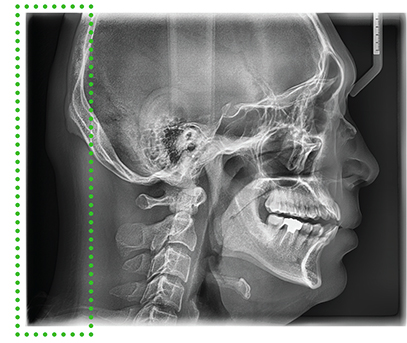

Цефалометрические изображения

Цефалометрическое сканирование предоставляет возможность получать не только стандартные боковые, но и расширенные боковые изображения черепа. Полные боковые снимки, или Full Lateral, превосходят обычные на 30%. Это позволяет улучшить качество ортодонтической диагностики за счёт более детального и точного анализа.